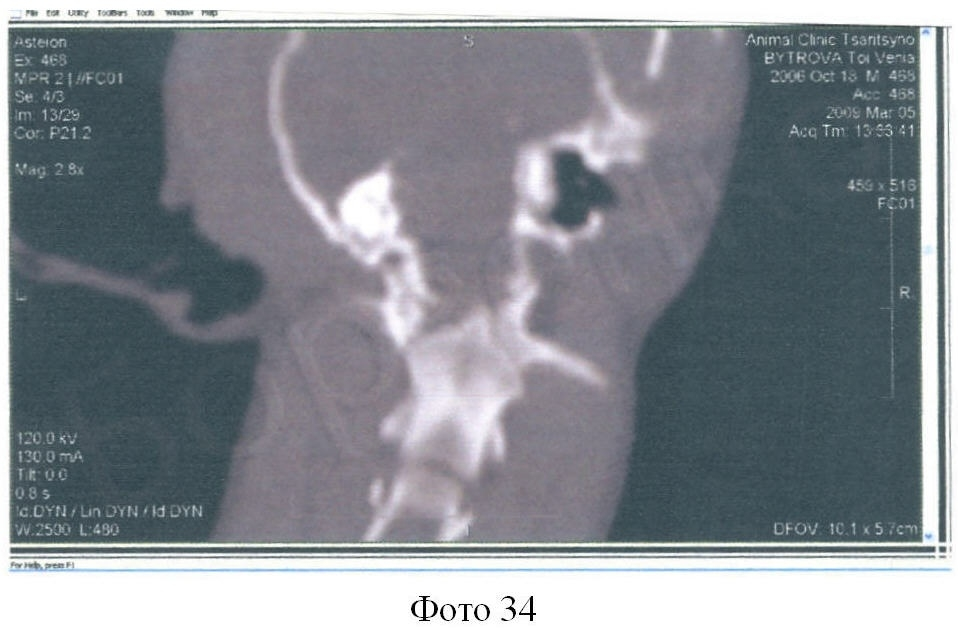

Компьютерная томография в диагностике краниовертебральных патологий

В процессе КТ исследования, пациент помещается на специальный стол, который затем перемещается внутри томографа. Во время сканирования рентгеновские лучи проникают через тело животного, и регистрируются детекторами, расположенными напротив исследуемой области. Затем полученные данные обрабатываются компьютером, который создает детальное изображение внутренних структур.

КТ позволяет выявить такие краниовертебральные патологии, как переломы позвонков, дегенеративные изменения, опухоли, воспалительные процессы, аномалии развития и другие расстройства. Благодаря возможности получения трехмерных изображений, КТ позволяет более точно определить локализацию и характер патологии, что является важным при планировании хирургического вмешательства или назначении лечения.

Преимущества КТ в диагностике краниовертебральных патологий: Высокая детализация изображений Возможность получения трехмерных изображений Высокая точность диагностики Безопасность для пациента Возможность проведения исследований с контрастными веществами При проведении КТ исследования животное должно быть подготовлено, что включает анестезию для ограничения движений, чтобы получить более четкое изображение. Во время исследования необходимо обеспечить максимально возможное удобство и безопасность пациента.

Компьютерная томография является важным методом диагностики краниовертебральных патологий у собак и кошек, который позволяет получить точные и детальные данные об обнаруженной патологии. Она является незаменимым инструментом в руках ветеринарного врача для принятия правильного диагноза и планирования эффективного лечения.

Преимущества компьютерной томографии заключаются в возможности получения срезов в различных плоскостях и объемных реконструкций, что позволяет более полно и точно изучить анатомические особенности и патологические изменения в краниовертебральной области.

Особенности компьютерной томографии также состоят в возможности использования контрастных веществ и создания 3D-моделей, что дает дополнительную информацию о состоянии патологических изменений. КТ является очень чувствительным методом диагностики, который позволяет обнаружить даже минимальные аномалии в краниовертебральной области.

Компьютерная томография широко используется в ветеринарной медицине для диагностики патологий позвоночника, головного мозга, лицевых костей и других структур. Она позволяет определить природу и локализацию повреждений, выявить опухоли, воспалительные процессы, деформации костей и тканей.